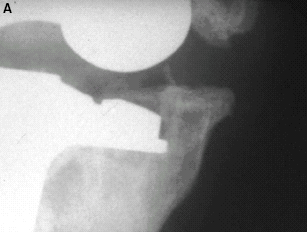

The most frequent complication of total ankle arthroplasty in the past has

been loss of bone support.

Fig 1: Talar component subsidence.

Most orthopaedic prostheses depend primarily on bone for support.

Unfortunately, however, many patients needing prosthetic arthroplasties have

weakened or compromised bone. Past experience with total ankle arthroplasty

has shown that loss of support is a primary reason for failure (Fig. 1).